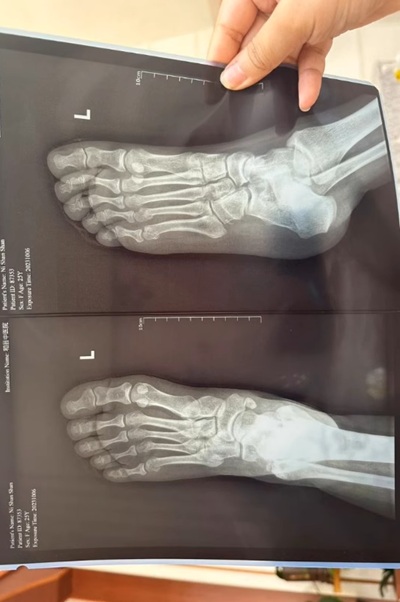

What Are Gout And Pseudogout?

Gout and pseudogout are both forms of arthritis caused by crystal deposition in the joints.

Gout typically affects the big toe (especially the joint at the base of the toe), but it can also affect the knees, ankles, and other joints.

Pseudogout often causes pain in the knees, wrists, elbows, and shoulders. It typically affects larger joints, unlike gout which affects smaller ones like the big toe.